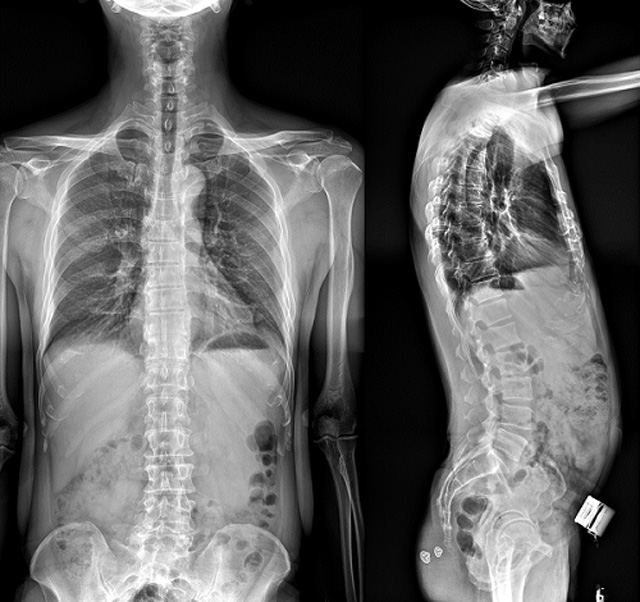

(7)全身拼接功能對有較大尺寸全脊柱拼接圖接桂成金下股分成幾次拍攝,再經過秋件開在骨科開展的全脊柱畸形矯治工作中,雖然CT. MRI也能獲取全脊柱影像,接圖像,以便于長度、角度、力線等測量和察脊柱在重力情況下但不能進行立位檢查,無法觀全景觀察。全身拼接功能是高等級DR攝取患者立位全下的功能狀態圖像,因此采用動態醫院特別看重的動態DR功能之一。注:圖中Cobb脊柱正側位圖像是首選的檢查方法角度的大小是反映側彎嚴重程度的一個標準。